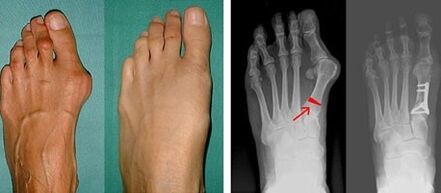

In the first stage of identifying valgus of the big toe and little toe, the doctor carries out a visual examination.In this way it determines the stage of development of the pathology.To identify detailed changes in the joints, x-rays and plantography are prescribed.

If the visual examination and x-rays give no results, the patient is referred for plantography to determine any flat feet.This method involves taking impressions of the feet, on the basis of which shoes or insoles with orthopedic properties are made for the patient.The patient is then prescribed podometry.This method uses computer analysis to determine the pressure of a person's weight on their feet.The results of advanced diagnostics form the basis for choosing a treatment method for the curvature of the first and second fingers.

The disadvantage of radiographic examination is the need to irradiate the patient's legs, which many patients do not like.They think this is too harmful a method.In this regard, effective treatment of hallux valgus cannot be started without the results of plantography.